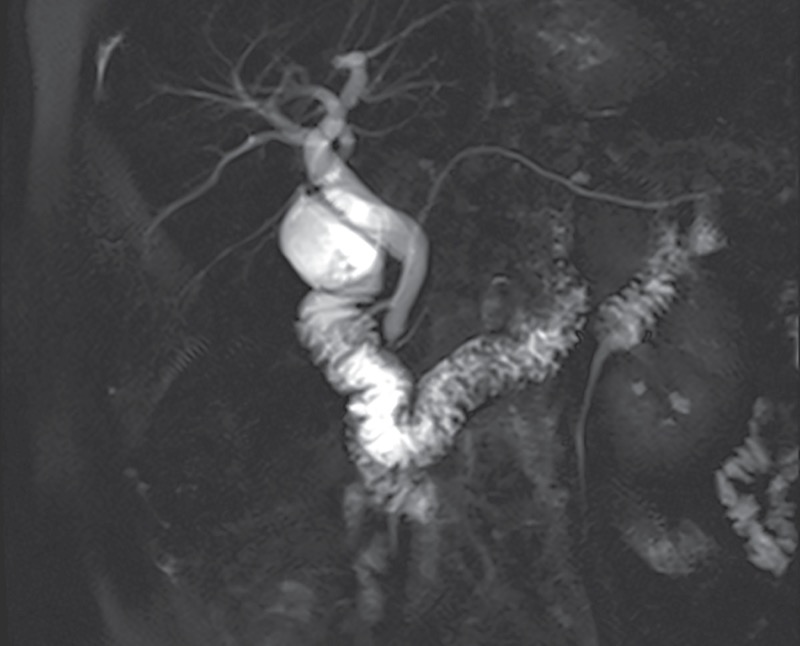

PD, the failure of the dorsal and ventral buds to fuse during organogenesis, is the most frequent congenital variation of pancreatic anatomy. It results in drainage of most of the pancreatic exocrine juice through the dorsal pancreatic duct and into the duodenum through the minor papilla.54 Autopsy series suggest that PD is found in 5% to 10% of the general population.55-58

MRCP and S-MRCP are usually the diagnostic modalities of choice for PD, given their noninvasiveness (Figure 4). Studies have demonstrated the high diagnostic accuracy of S-MRCP.65-67 Mosler et al found that S-MRCP had an overall sensitivity and specificity of 73% and 97%, respectively, when compared with ERCP in 19 patients.65 The sensitivity and specificity improved to 83% and 99% in the subgroup of patients without CP. A meta-analysis and systematic review of 11 studies evaluating the utility of MRCP, S-MRCP, and EUS found similar results, with specificities of 99% for both MRCP and S-MRCP but a higher sensitivity of S-MRCP (83% vs 59%).66 Data also suggest that S-MRCP could help identify a subgroup of patients who might respond to endoscopic therapy, as evidenced by a recently published retrospective study from 3 tertiary centers in China evaluating 120 patients with PD who underwent endoscopic retrograde pancreatography.67 The investigators found that linear array EUS had a sensitivity of 90.8%, a specificity of 99.8%, and an overall diagnostic accuracy of 99%, suggesting it is a reasonable alternative to S-MRCP. They also noted that the degree of duct dilation suggested an obstructive process and might correlate with or predict a response to minor papilla intervention, but this assumption has not been proven conclusively to date.